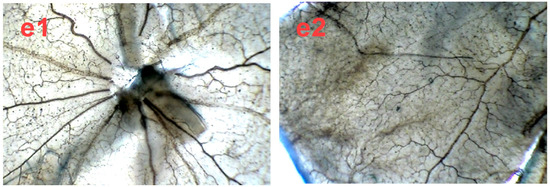

Figure 6.

The in vivo effect of SPN and Conbercept on retinopathy of rats in ADPase-stained retinal sections (40×). Central retinal region of rat pups fostered under normoxia conditions (a1); OIR rats intraperitoneally administered with NS (b1), 1.0 mg/kg Conbercept (c1), 5.0 mg/kg SPN (d1) or 10.0 mg/kg SPN (e1). Peripheral retinal region of control, rat pups fostered under normoxia conditions (a2); OIR rats intraperitoneally administered with NS (b2), 1.0 mg/kg Conbercept (c2), 5.0 mg/kg SPN (d2) or 10.0 mg/kg SPN (e2). Ten rats were used for each group (n = 10).

After we demonstrated the inhibitory effect of SPN on VEGFA secretion in ARPE-19 cells in vitro, next, we further investigated the preventive effect of SPN on the hypoxia-induced retinal neovascularization with superficial vascular plexuses using ADPase staining in a rat pup model. The rat pups were exposed to 80% oxygen from postnatal day (PD) 7 to PD 12 to produce retinal and then returned to room air. This condition made the retina relatively hypoxic, resulting in the formation of retinal neovascularization. On PD 17, the OIR rats treated with vehicle increased the total retinal neovascular areas significantly compared to that of the normal rats treated with the vehicle (p < 0.01), whereas SPN markedly reversed the hypoxia-induced total neovascular areas , and the ratio of retinal neovascularization in a dose-dependent manner (Figure 5a,b). Furthermore, SPN significantly alleviated the neovascularization, vessel tortuosity, and dilated vessels of the OIR rats (Figure 6).